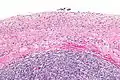

| Ovarian serous cystadenoma. The cystic space is at the top of the image. Ovarian parenchyma is seen at the bottom right. H&E stain. | |

Serous cystadenomas are diagnosed by histomorphologic examination, by pathologists. Grossly, they are, usually, small unilocular cysts that contain clear, straw-coloured fluid. However, they may sometimes be multilocular. Microscopically, the cyst lining consists of a simple epithelium, whose cells may be either:[3]

- be columnar and tall and contain cilia, resembling normal tubal epithelium

- be cuboidal and have no cilia, resembling ovarian surface epithelium